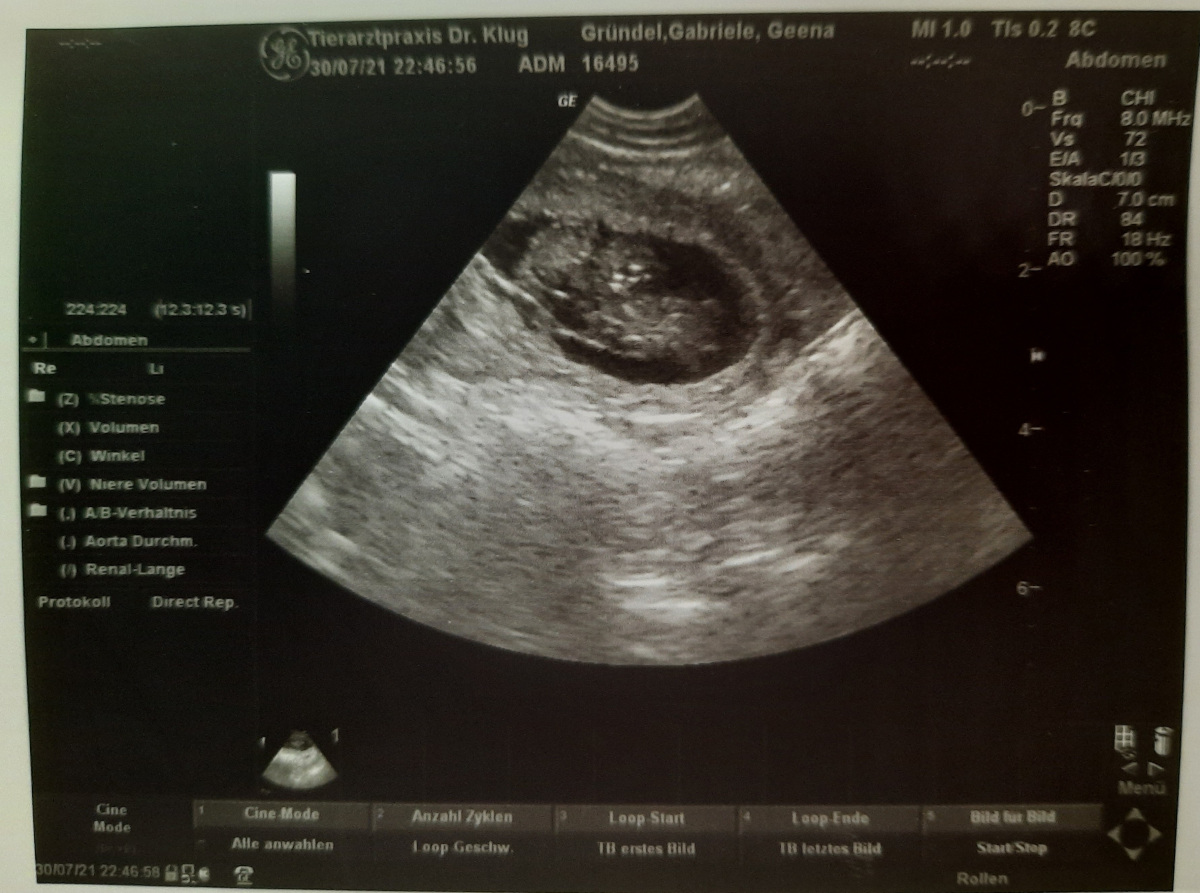

Heute waren wir mit Geena zum Ultraschall, wir freuen uns sehr das die Hochzeit von Hennessy von Anluna’s & Kju ay’s Geena Davis Früchte trägt. Wir erwarten um den 4. September unseren L-Wurf.